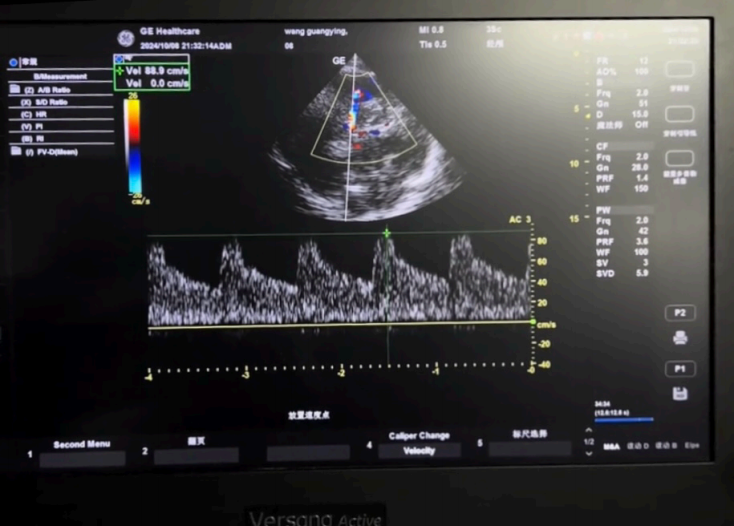

圖4:?腦中動脈(MCA)?流速:評估腦?流(操作者:吳威)